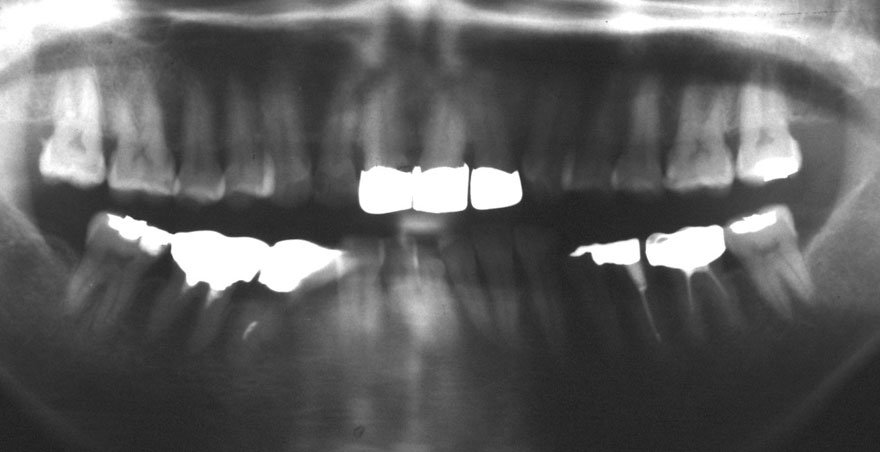

開始年齢 40代

初診時 40歳 女性 平均歯槽骨喪失量:3.14mm

32年後 72歳

平均歯槽骨喪失量:3.22mm

32年間喪失量:-0.08mm

年間喪失速度:-0.002mm

(ケア頻度:1.86ヵ月ごと)